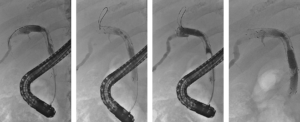

Een 68-jarige vrouw werd verwezen in verband met verdenking op een perihilair cholangiocarcinoom, Bismuth type IIIb (figuur 1). In verband met icterus en mogelijke hemihepatectomie links werd er een plastic endoprothese in de rechter ductus hepaticus geplaatst. De galwegen links werden bewust niet gecontrasteerd. Tevens werd een brush afgenomen die de diagnose adenocarcinoom bevestigde. Vanwege snel toegenomen vaatbetrokkenheid kwam patiënte niet meer in aanmerking voor resectie of levertransplantatie. Derhalve werd gestart met palliatieve systeemtherapie en werd de plastic stent electief gewisseld voor een ‘uncovered’ metalen stent (uSEMS). Aangezien er, op basis van het lage bilirubinegehalte (11 μmol/L), reeds voldoende drainage met een unilaterale stent was bereikt, werd er niet aanvullend bilateraal gedraineerd. In studieverband (RACCOON-pilot [NL9144]) werd de stenose geableerd met endobiliaire radiofrequente ablatie (eRFA), met het doel om de duur van de stentdoorgankelijkheid te verlengen. Met een 22 mm ELRA-electrode (Taewoong Medical) werd de stenose 90 seconde geableerd met 7 watt en target temperatuur van 75 graden (figuur 2). De ductus cysticus werd niet in het traject betrokken om een post-procedurele cholecystitis te voorkomen. Na verwijderen van necrotisch materiaal met een extractieballon werd een 80 x 8 mm uSEMS geplaatst (figuur 3). 5 maanden later ontwikkelde patiënte klachten passend bij stentobstructie. Er werd opnieuw eRFA verricht van de stenose in de stent en een tweede 60 x 8 mm uSEMS in de reeds aanwezige stent geplaatst (figuur 4). Weer 5 maanden later ontwikkelde patiënte recidiverende klachten. Er werd opnieuw eRFA verricht, maar ditmaal werd geen aanvullende stent geplaatst (figuur 5). Patiënte overleed 5 maanden later zonder terugkerende obstructie, 2 jaar na de diagnose.